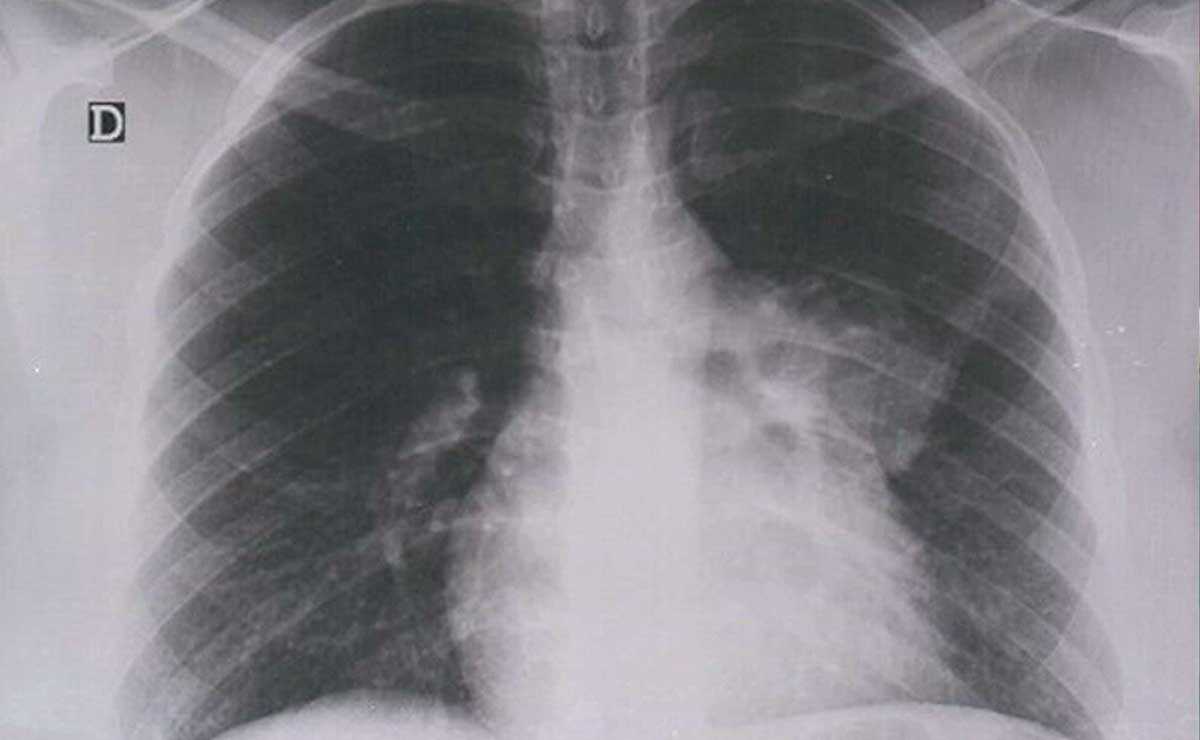

De acuerdo con los cálculos de organismos internacionales, el cáncer de mama, próstata, cervicouteriuno, colorrectal y pulmón son los más recurrentes en la población de ambos sexos.

-Pulmón, con una incidencia de 6.5 por cada 100 mil hombres.